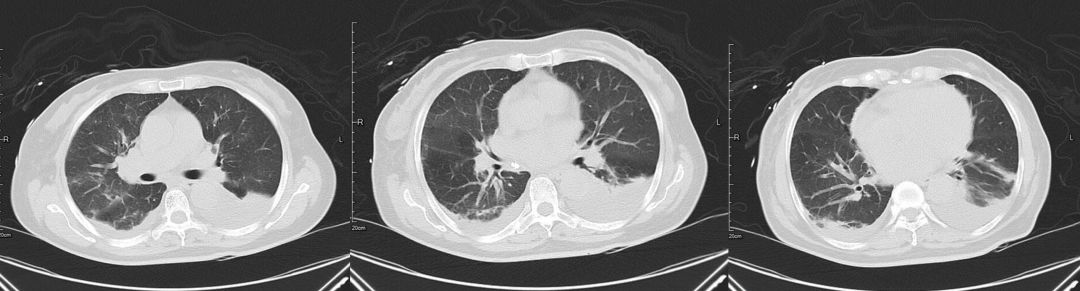

治疗后(2019-03-08)

患者咳嗽、胸闷症状明显缓解,3天后复查胸部CT提示肺部渗出影较前明显吸收。

5、多学科会诊后,加强心衰方面治疗,患者临床症状明显缓解,且胸部影像学短期较前相比明显吸收。后期复查心超发现赘生物,需进一步外科干预,因患者合并脑出血,暂缓手术,予内科保守治疗。

肿瘤细胞浸润间质所致,咳嗽、咳大量粘液性泡沫性痰,病理可以明确鉴别。该病例中影像学表现密度相对均匀,与大叶性肺炎相比密度稍低,应用加强利尿3天后肺内磨玻璃影迅速吸收,变化快,肺部感染一般需2周甚至更长时间才能吸收,从影像特点及治疗后的反应上来讲均不支持肺炎。